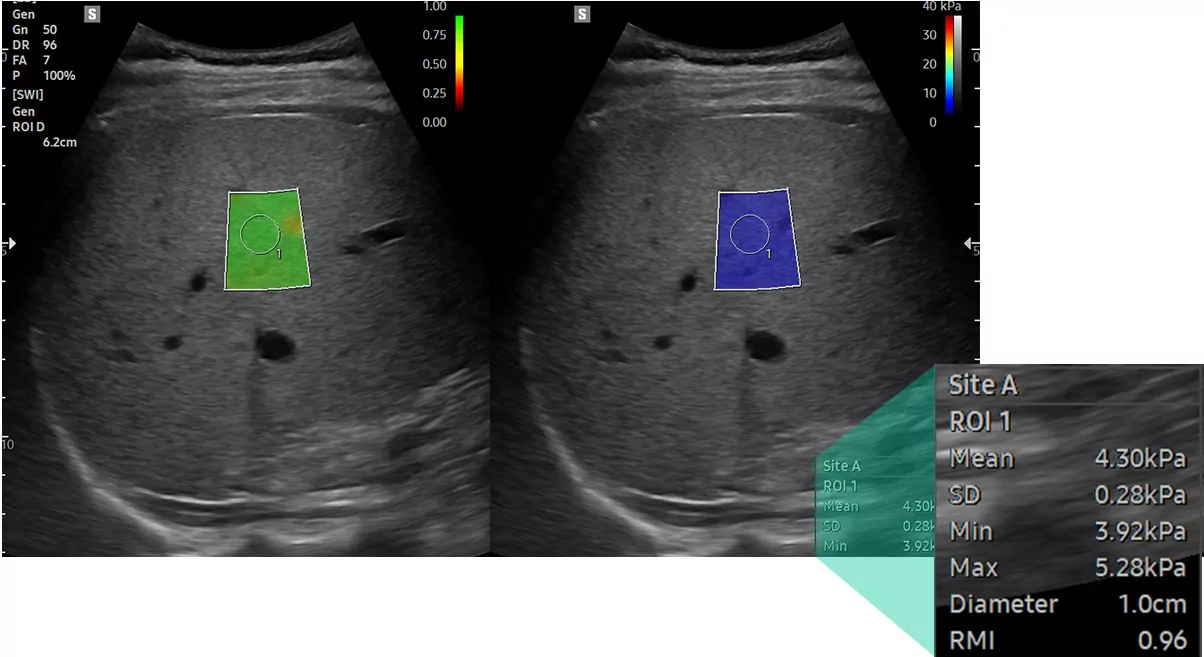

S-Shearwave Imaging™ дозволяє проводити неінвазивну оцінку жорстких тканин у різних застосуваннях. Еластограма з кольоровим кодуванням, кількісні вимірювання, параметри відображення та функції ROI, які вибирає користувач, особливо корисні для точної діагностики захворювань молочної залози та печінки.

Печінка з S-Shearwave Imaging™